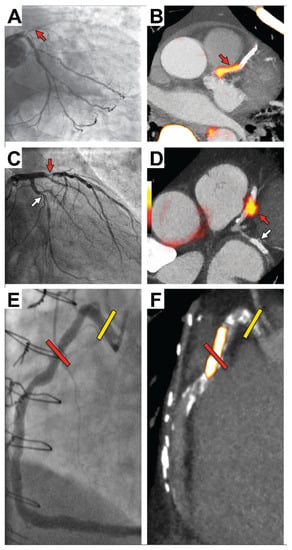

- Joshi, N.V.; Vesey, A.T.; Williams, M.C.; Shah, A.S.V.; Calvert, P.A.; Craighead, F.H.M.; Yeoh, S.E.; Wallace, W.; Salter, D.; Fletcher, A.M.; et al. 18F-fluoride positron emission tomography for identification of ruptured and high-risk coronary atherosclerotic plaques: A prospective clinical trial. Lancet 2014, 383, 705–713. [Google Scholar] [CrossRef] [PubMed]

- Lee, J.M.; Bang, J.-I.; Koo, B.-K.; Hwang, D.; Park, J.; Zhang, J.; Yaliang, T.; Suh, M.; Paeng, J.C.; Shiono, Y.; et al. Clinical Relevance of 18 F-Sodium Fluoride Positron-Emission Tomography in Noninvasive Identification of High-Risk Plaque in Patients with Coronary Artery Disease. Circ. Cardiovasc. Imaging 2017, 10, e006704. [Google Scholar] [CrossRef] [PubMed]

- Kwiecinski, J.; Dey, D.; Cadet, S.; Lee, S.-E.; Tamarappoo, B.; Otaki, Y.; Huynh, P.T.; Friedman, J.D.; Dweck, M.R.; Newby, D.E.; et al. Predictors of 18F-sodium fluoride uptake in patients with stable coronary artery disease and adverse plaque features on computed tomography angiography. Eur. Hear. J.-Cardiovasc. Imaging 2019, 21, 58–66. [Google Scholar] [CrossRef] [PubMed]

- Kwiecinski, J.; Tzolos, E.; Cadet, S.; Adamson, P.D.; Moss, A.; Joshi, N.V.; Van Beek, E.; Williams, M.; Berman, D.S.; Newby, D.E.; et al. 18F-sodium fluoride coronary uptake predicts outcome in patients with coronary artery disease. J. Am. Coll. Cardiol. 2020, 75, 3061–3074. [Google Scholar] [CrossRef]

- Kwiecinski, J.; Tzolos, E.; Meah, M.N.; Cadet, S.; Adamson, P.D.; Grodecki, K.; Joshi, N.V.; Moss, A.J.; Williams, M.C.; van Beek, E.J.R.; et al. Machine Learning with 18F-Sodium Fluoride PET and Quantitative Plaque Analysis on CT Angiography for the Future Risk of Myocardial Infarction. J. Nucl. Med. 2022, 63, 158–165. [Google Scholar] [CrossRef]